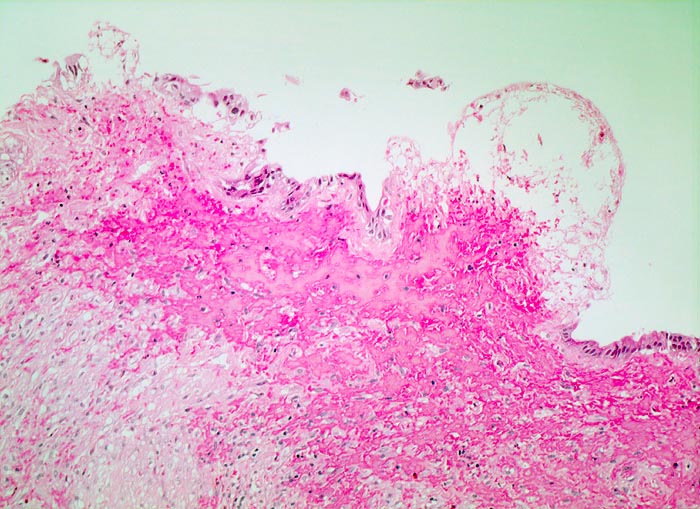

chronische Cholezystitis mit Steineindruckstelle

Entzündung / Reparatur

Gallenblase

Das Schleimhautrelief ist abgeflacht. Steineindruckstelle mit druckbedingtem Ulkus mit Ablagerung von Fibrin und Einblutung im Ulkusgrund.

Wiederholte rechtsseitige Oberbauchbeschwerden.

Histologie

100